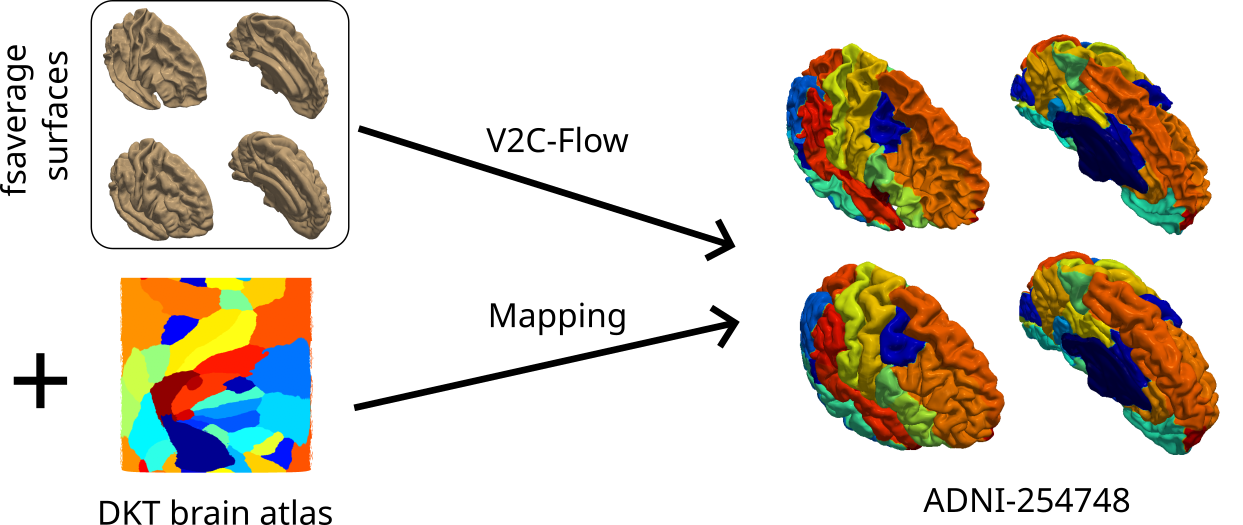

5.5 Surface parcellation

The parcellation of the cortex according to a reference atlas, e.g., the popular DKT atlas [7, 26], supports region-wise analyses. More precisely, it enables a fine-grained evaluation of morphological measurements like cortical thickness in individual brain regions and draws connections between structural changes and brain functionality. In this work, we propose and evaluate two different ways of creating a parcellation of V2C-Flow surfaces (see Supplementary Figure 4 for a visualization of both methods). First, we exploit the learned correspondences between the folded fsaverage template and predicted surfaces by mapping vertex classes directly from the template atlas onto the predicted mesh. This can be done immediately, i.e., without any further processing, and it is therefore the fastest option. We call this method direct mapping. Second, we exploit the correspondences between the predicted surfaces to the spherical representation of the fsaverage template. These correspondences allow for curvature-based registration of the predicted surface to the template sphere as implemented in FreeSurfer’s mris_register without having to inflate each predicted surface separately (which makes up a large amount of the processing time in FreeSurfer). We call this method registration-based. We assess the accuracy of the proposed methods on the ADNI test set with respect to the FreeSurfer DKT parcellation in terms of Dice overlap. As a baseline, we use FastSurfer v1.1.2 [20] in this case.

For the mapping-based approach, we obtain an average Dice coefficient (weighted according to region sizes) of 0.82(SD=0.030)0.82SD0.0300.82\ (\text{SD}=0.030) and 0.83(SD=0.029)0.83SD0.0290.83\ (\text{SD}=0.029) for left and right hemispheres, respectively. This is surprising given that we did not optimize for this task at training time nor did we use any post-processing. However, if a higher parcellation accuracy is required, the quality can be further improved to an average Dice of 0.89(SD=0.020)0.89SD0.0200.89\ (\text{SD}=0.020) and 0.89(SD=0.023)0.89SD0.0230.89\ (\text{SD}=0.023) per hemisphere by using the registration-based parcellation approach. This approach outperforms FastSurfer, which yields Dice scores of 0.87(SD=0.015)0.87SD0.0150.87\ (\text{SD}=0.015) and 0.88(SD=0.022)0.88SD0.0220.88\ (\text{SD}=0.022) for left and right hemispheres, respectively. In addition, we observe in Supplementary Figure 5 that the misclassification of vertices occurs exclusively at the parcel boundaries, which are typically most susceptible to inter-rater variability. That is, the generation of anatomically implausible “islands” is effectively prevented. We conclude that it is straightforward to perform brain parcellation with V2C-Flow, since it maps a template to individual surfaces and not vice-versa, which is in contrast to most existing methods. Both of the proposed parcellation methods eliminate the need for intricate surface inflation by exploiting learned correspondences to the input template. In practice, the question of which method to choose boils down to an accuracy-speed trade-off: the mapping-based method is as fast as it can get while the registration-based approach yields higher accuracy — surpassing FastSurfer in terms of parcellation Dice.